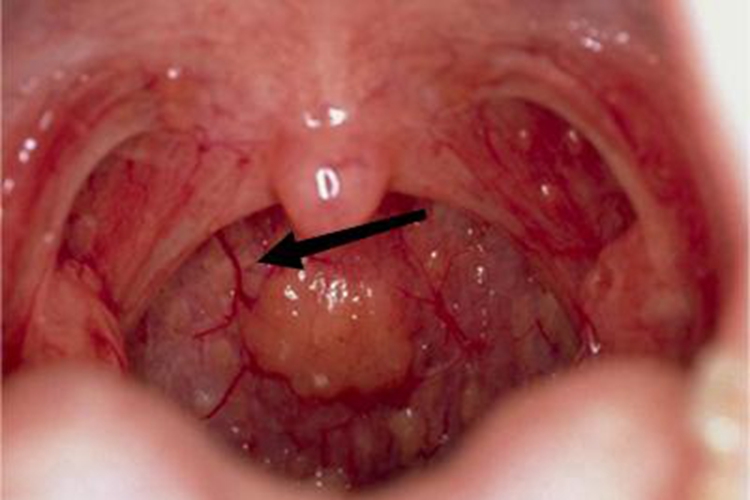

慢性咽炎可见咽部黏膜充血,有血丝,咽后壁有凸起的包块。该病多因急性咽炎反复发作所致,可遵医嘱应用药物进行治疗。

慢性咽炎患者可出现咽部异物感、痒感、干燥感等,检查时可以看到咽部黏膜充血、增厚,有血丝,咽后壁淋巴滤泡显著增生,会有凸起的包块形成,咽侧索亦充血肥厚。